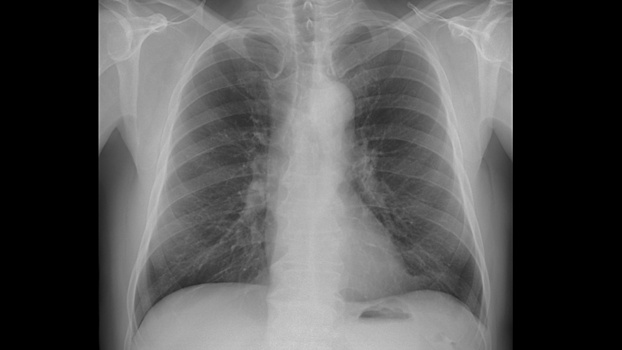

Технология искусственного интеллекта позволяет автоматизировать обработку результатов компьютерной томографии, рентгенографии и маммографии. Благодаря ей любые изменения на снимках, сигнализирующие о возможном наличии патологий, оперативно обнаруживаются. Также формируется подробное заключение, что повышает точность диагностики и качество оказания медицинских услуг.

Сервис был подключён более чем в 30 государственных медицинских учреждениях: больницах, поликлиниках и диспансерах Вологды. Для этого был настроен электронный обмен лучевыми снимками между местной медицинской системой и московской платформой. Только за первый месяц использования сервиса на базе искусственного интеллекта было обработано более трех тысяч медицинских снимков (рентгенологических и маммографических исследований, компьютерной томографии).

Использование платформы искусственного интеллекта позволяет достичь высокой скорости и точности обработки медицинских изображений — до 95 %. Кроме того, система обладает возможностью анализа большого объема данных, важным преимуществом также является автоматическая графическая маркировка выявленных патологических изменений и формирование подробных заключений.